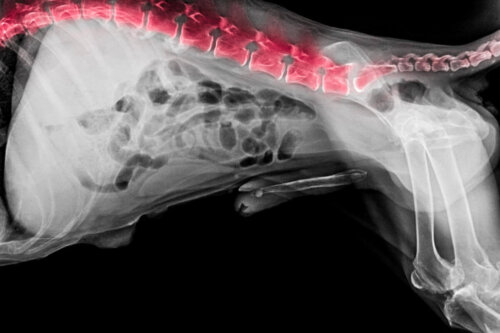

W klinice przeprowadza się szereg podstawowych badań w celu ustalenia przyczyny urazu. Najczęstszym jest zdjęcie rentgenowskie, za pomocą którego diagnoza różnicowa jest weryfikowana z innymi przyczynami, które mogą dawać podobne objawy, takimi jak guzy lub złamania. Konieczne może być również tomografia komputerowa lub rezonansu magnetycznego.